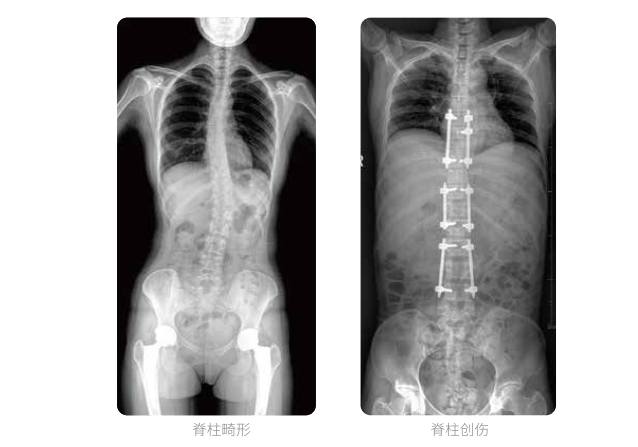

PLX8600大视野平板动态DR全脊柱一次成像摄片适用于儿童、成人、老年人腰椎退行性病变、强直性脊柱炎、脊柱结核等临床应用,在此类大视野的临床拍摄中发挥了极大的价值。

PLX8600大视野平板动态DR可在透视情况下多角度观察病灶部位,做术前诊断及术后愈合的检查,如脊柱斜位透视,可观察椎弓根峡部,诊断椎体是否滑脱等情况;可在脊柱运动状态下通过透视模式观察全脊柱状态,了解病变处脊柱的活动度及骨结构的关系,配合点片功能快速获得高清的关键帧影像,辅助医生制定更准确的手术方案。